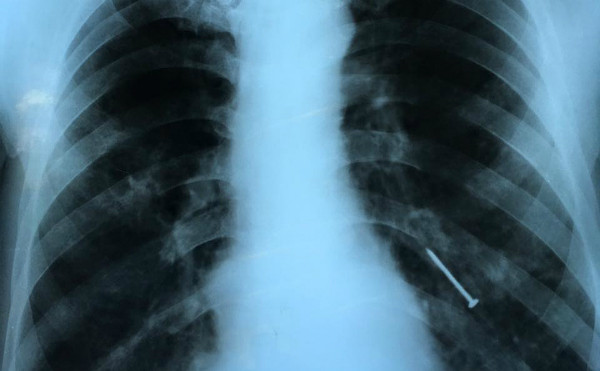

Hình ảnh X-quang cây đinh nằm ở phế quản bệnh nhân. Ảnh: V.T.

Bác sĩ Phạm Thị Vân Thanh, Khoa Nội soi, Bệnh viện Chợ Rẫy, TP HCM, cho biết bệnh nhân vào viện trong tình trạng ho liên tục 4 tháng, có lúc ho ra máu. Kết quả chẩn đoán hình ảnh phát hiện dị vật nằm ở phế quản thùy dưới bên trái.